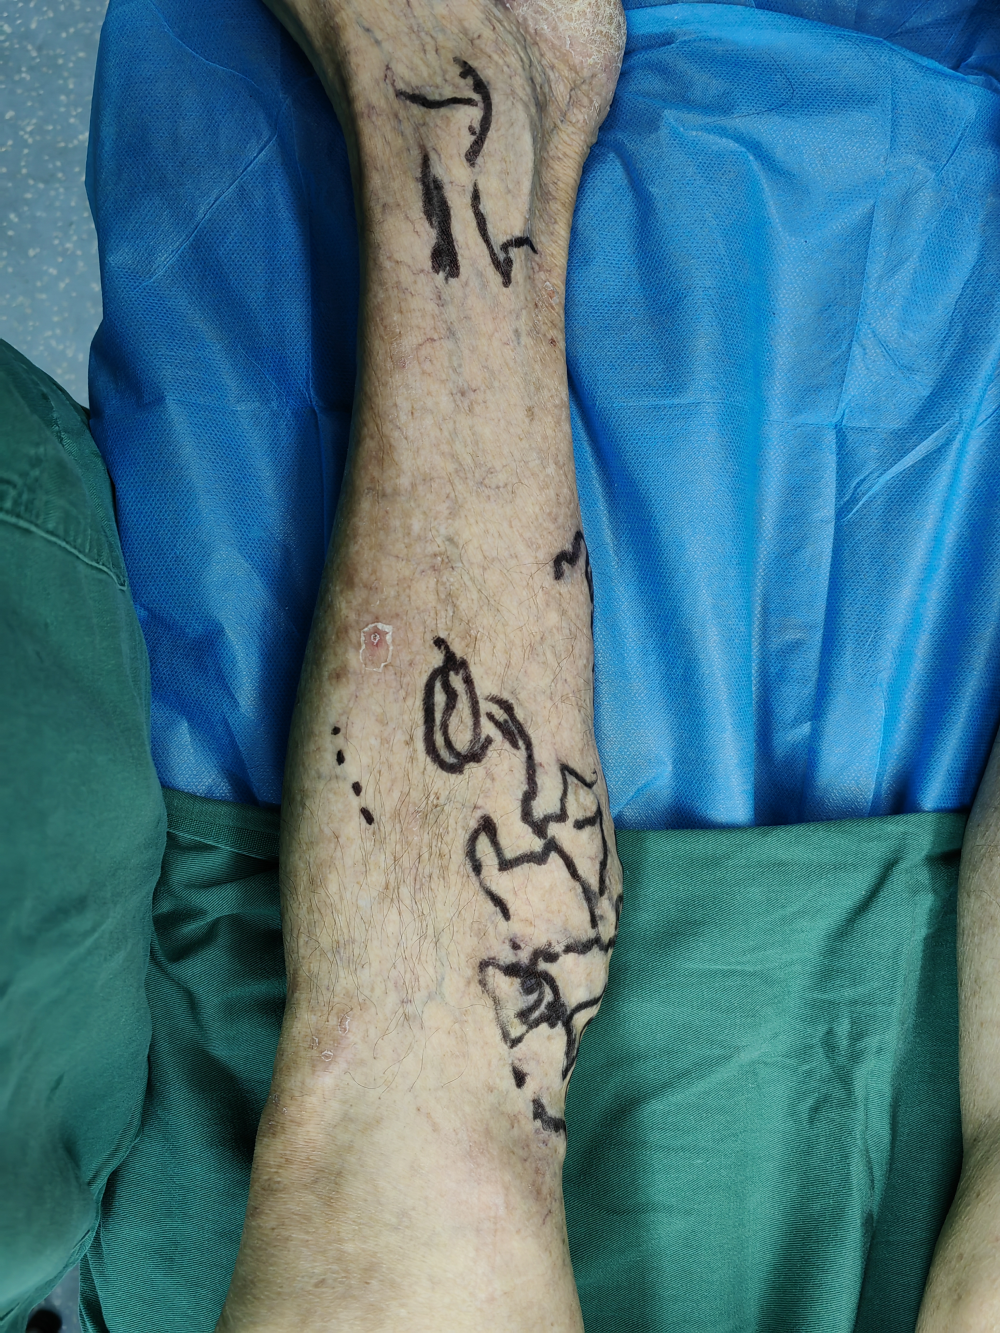

下肢(zhī)靜脈曲張(zhāng)為常見病及多發病(bìng),臨床表現主要為下肢血管迂曲、下肢腫脹(zhàng)、疼痛、局部皮膚色素沉著(zhe)、嚴重時出現(xiàn)局部潰瘍、潰(kuì)爛。對於(yú)有嚴重臨床表現者均需(xū)要手術治療。傳統(tǒng)手術為大隱(yǐn)靜脈高位結紮+主幹剝脫+曲張(zhāng)靜脈剝脫,相比微創手術其缺點是創傷大、恢複(fù)慢、下肢皮膚麻木感、不美觀等(děng)。我院外二科自2022年底始常規開展(zhǎn)下肢(zhī)靜脈微創手術,運用穿刺技術進行血管腔內消融閉合,硬化劑注射閉合曲張血管(guǎn),從而(ér)達到傳統手術一樣效果(guǒ),其優點為無切口、損傷小、恢複(fù)快、術後疼痛輕微、無明顯皮膚麻木感、美觀等。下肢靜脈曲張主要危險因素有:重體力勞動、長時間站立工作、體型粗大、妊娠(shēn)、長時間坐位工作等。預防下肢靜脈曲張(zhāng)措施有:改變工作方式,如需長時間站立或者坐位工(gōng)作(zuò)者,可以穿(chuān)靜脈曲張彈力襪;保持良好生活習慣,堅(jiān)持適當體育鍛煉等。外二科現常規開展血管外科相關手術,如下肢靜脈曲張微創手術、下肢靜(jìng)脈血栓相關手術治療、血管瘤/血管畸形介入治療(liáo)、下肢動脈常規介入手(shǒu)術、內髒血(xuè)管病變相關介入手術、內髒出(chū)血栓塞術等。

手術中